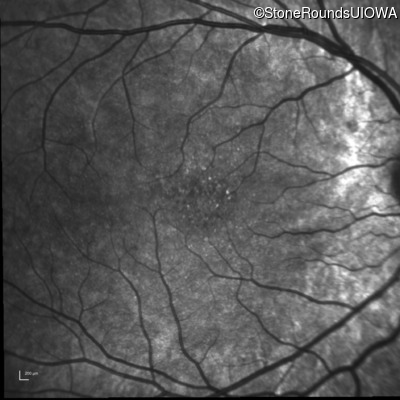

Infrared Fundus Photograph - Left - 20/40 sc

Exemplar